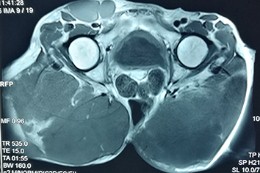

患者术前影像资料

第7次手术后两年,骶骨脊索瘤再次复发,患者已经失去了治疗的信心,选择消极应对,“不想再拖累老伴儿和孩子们了”。在接下来的4年时间里,肿瘤疯长,像两个巨大的肉球,挤压着臀部的肌肉和神经,走路都迈不开腿、睡觉无法平卧,最终导致小便*禁失**、大便无力,肿瘤的肿胀感也让患者无法安眠。

针对巨大的骶骨脊索瘤,神经外科联合泌尿外科、血管外科、胃肠外科、整形外科、重症医学科、麻醉科、放疗科、呼吸内科、输血科等学科专家,进行多次术前联合诊疗。手术困难重重,脊索瘤位于患者双侧臀部及右侧腹股沟区域,血供丰富,术中,保命的第一要务是避免大出血;此外,降低臀部的肌肉和神经受压迫的症状,以保证患者术后正常行走;再次,肿瘤与骨盆及邻近脏器关系紧密,切除过程中需特别注意肿瘤对膀胱、直肠、腹部大血管等的压迫或侵犯;最后,肿块巨大,切除后皮肤的缝合和愈合问题,术后的监护和治疗问题等,都是关系着预后的要点。